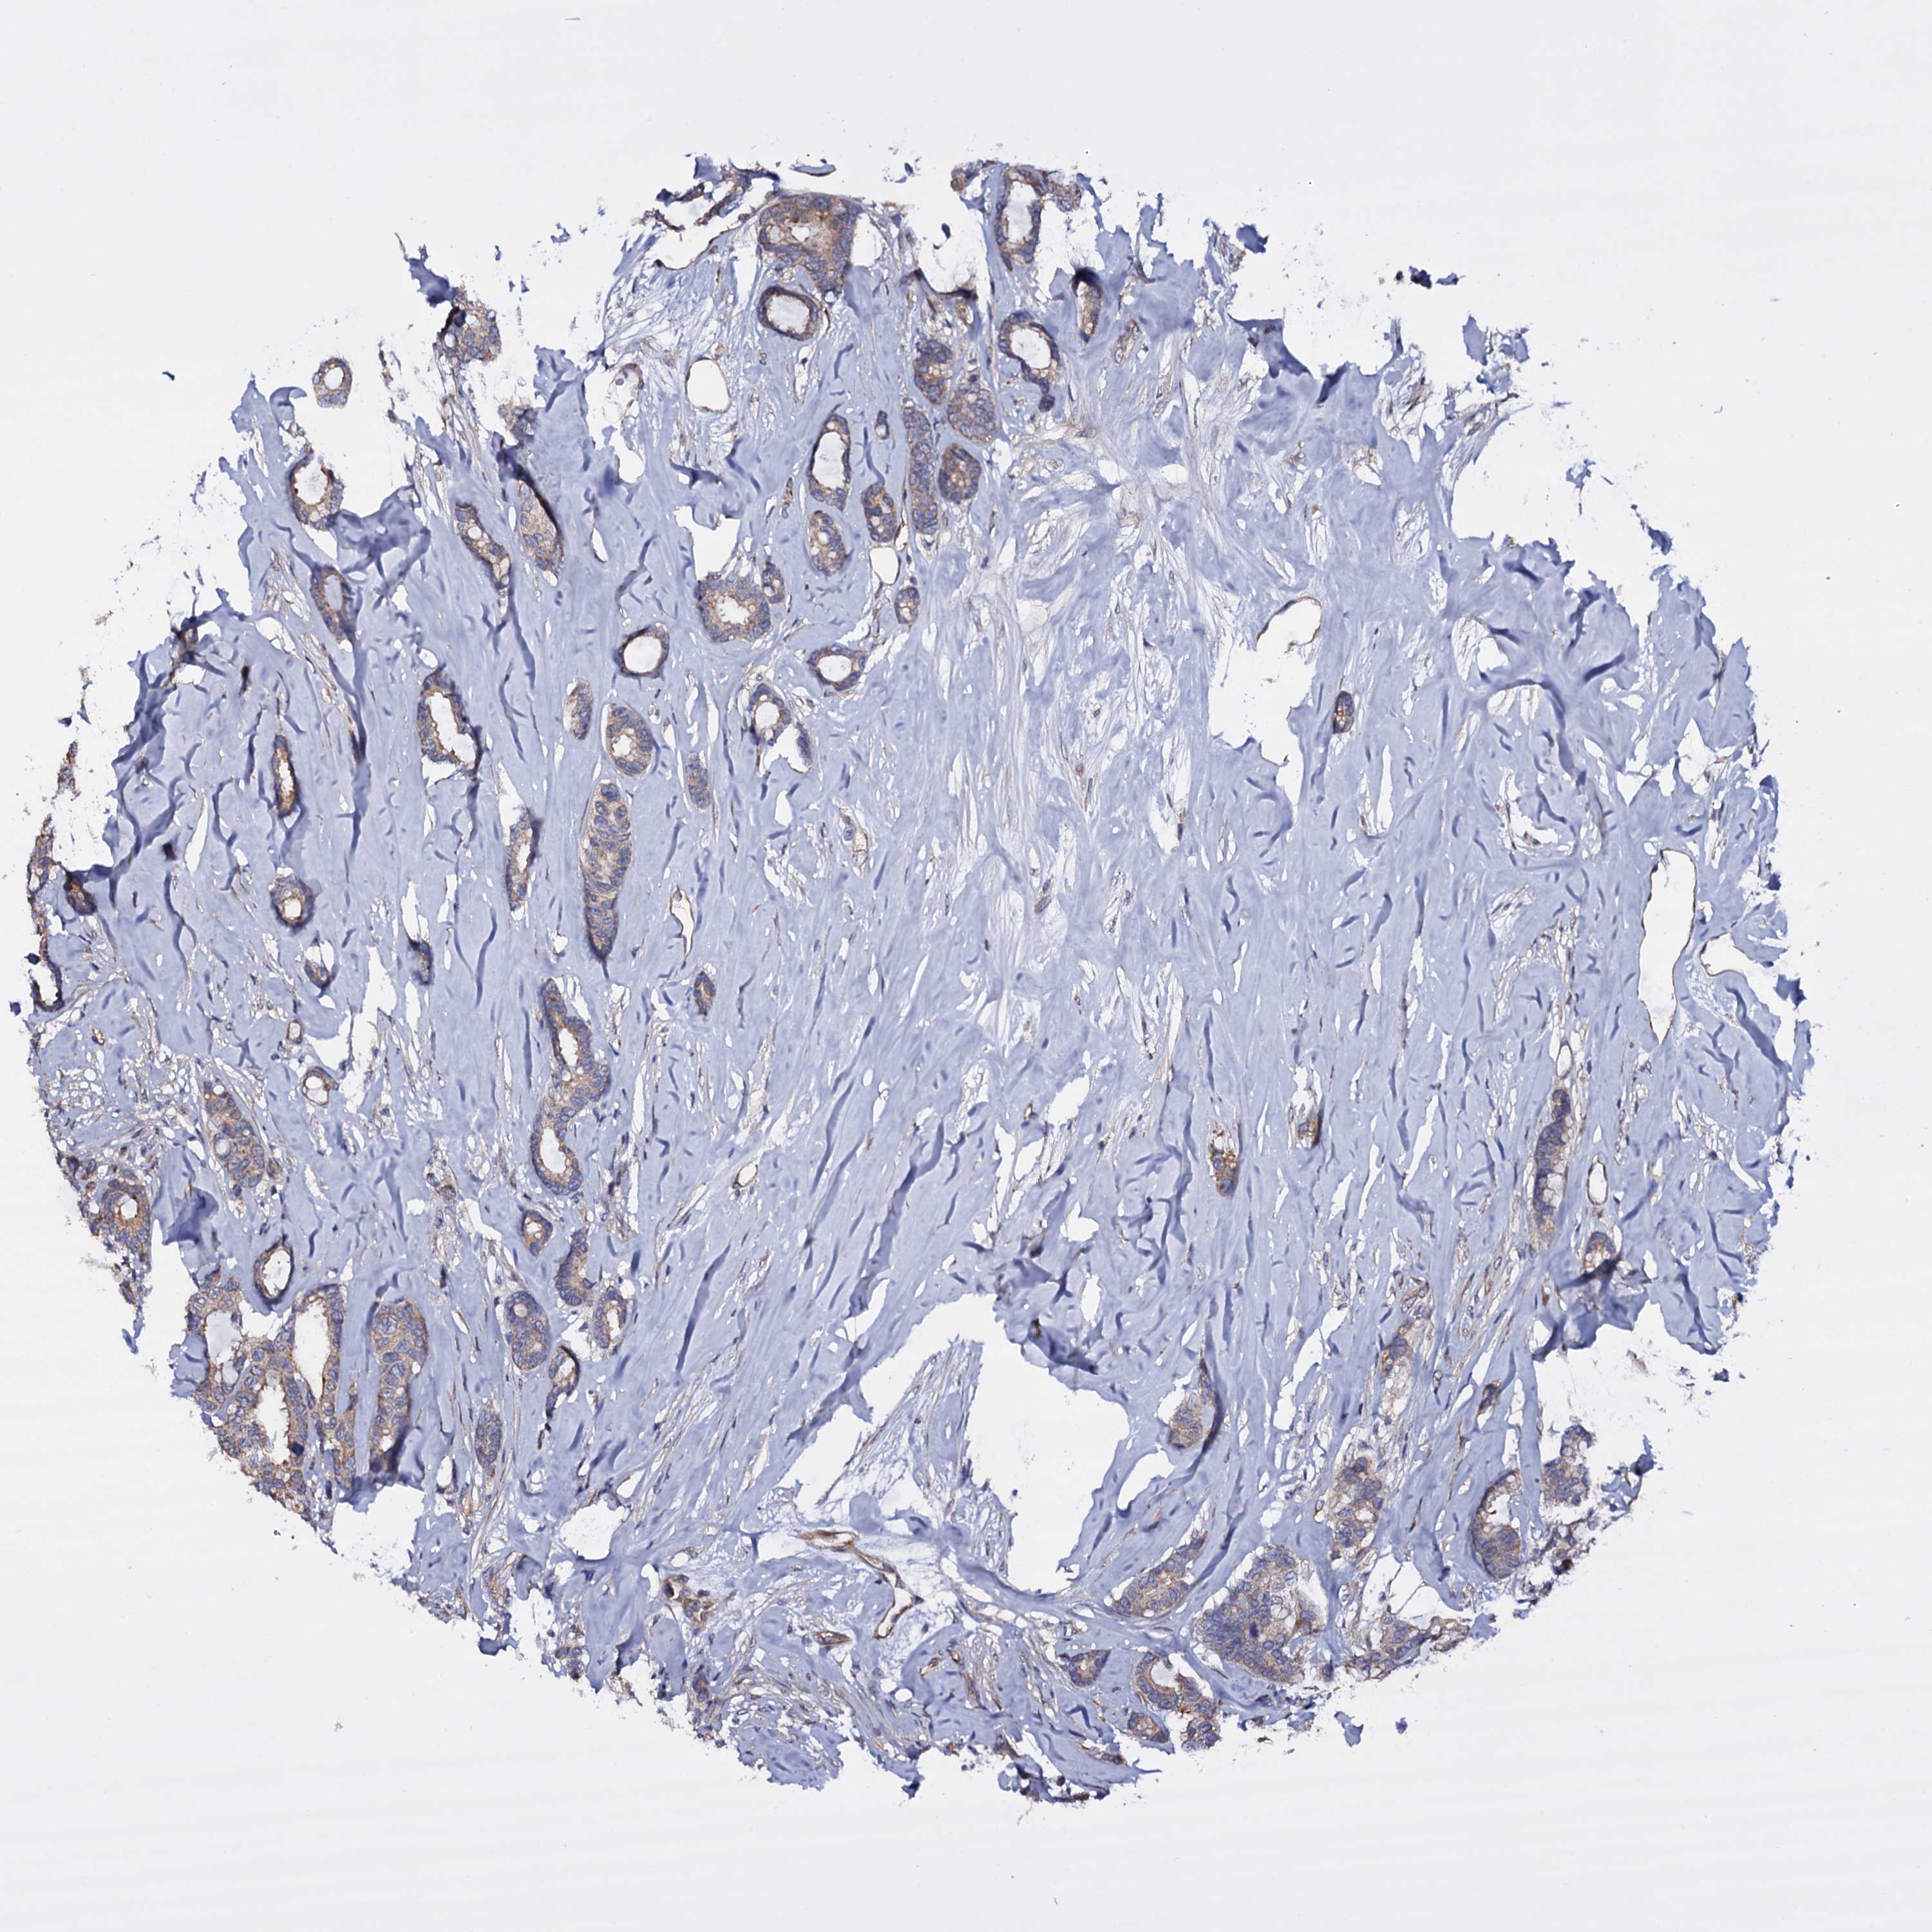

CANCER BREAST CANCER Show tissue menu

BRCA TCGA BRCA VALIDATION PROTEIN EXPRESSION